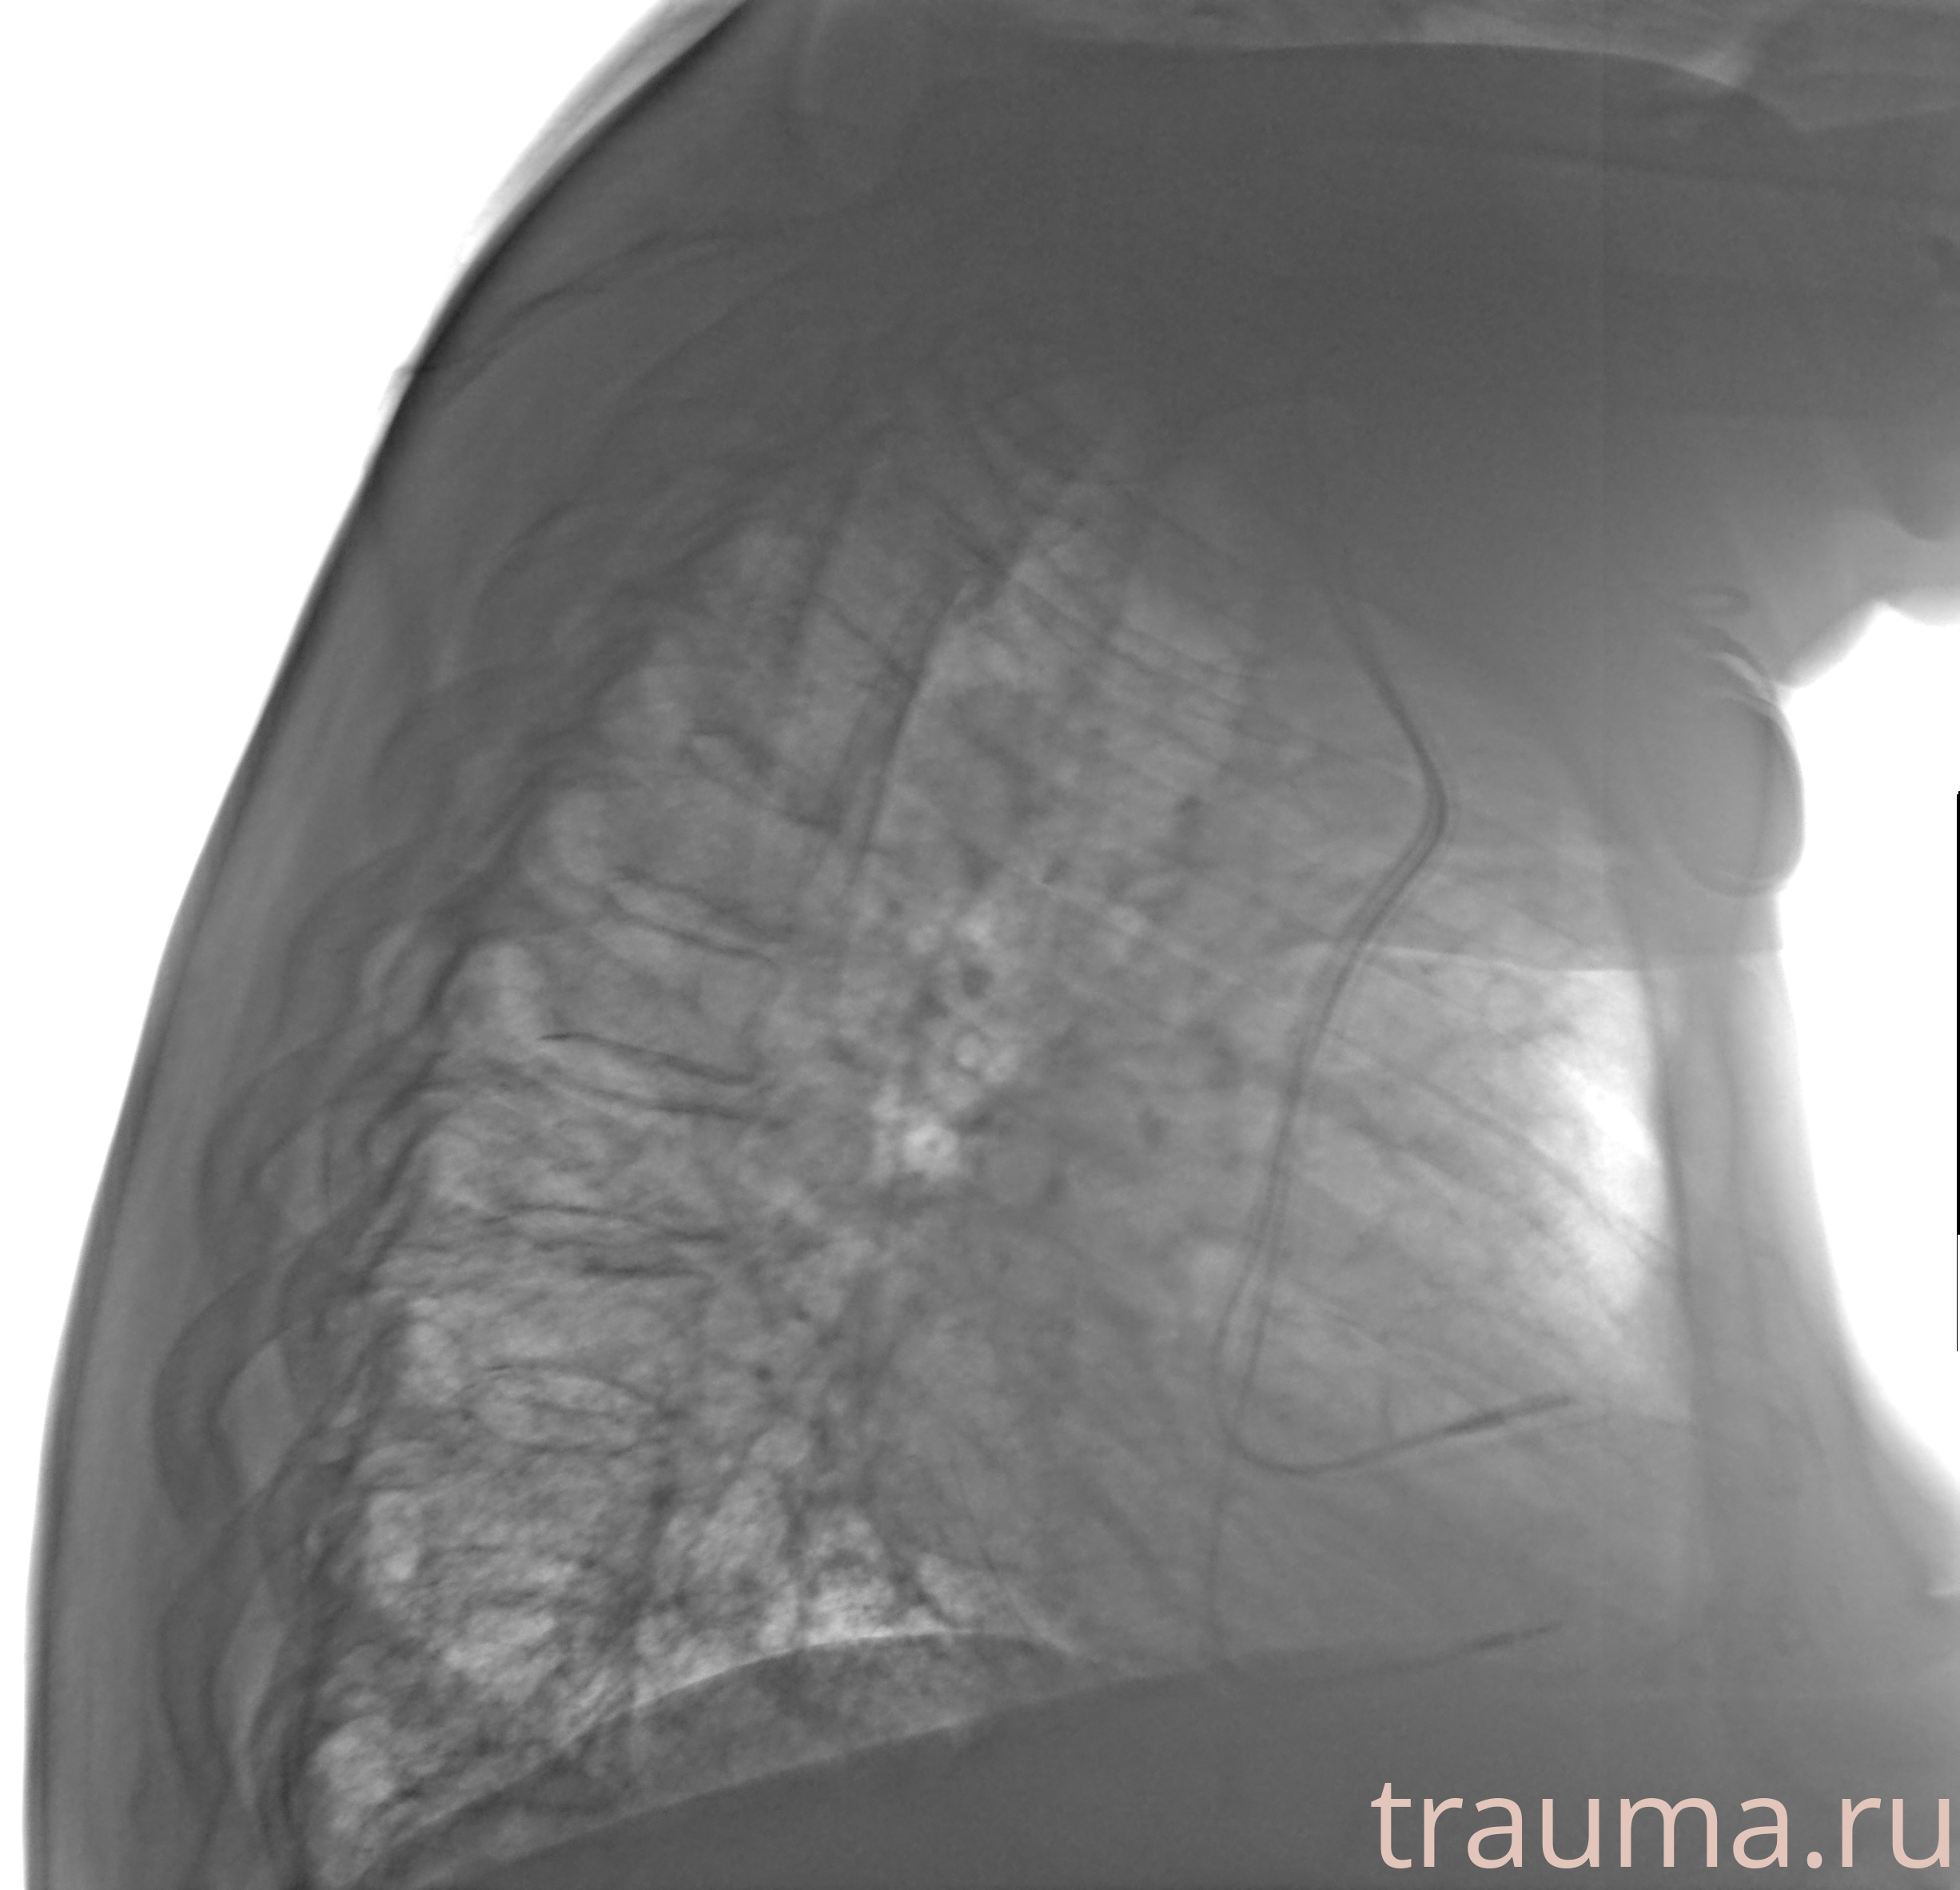

Рентген на дому: по вашему адресу приезжает врач-рентгенолог, травматолог-ортопед с мобильным рентгеновским аппаратом, проводит диагностику травмы или заболевания, делает необходимые рентгенограммы, дает рекомендации по дальнейшему лечению. Получить качественные снимки в домашних условиях возможно благодаря уникальной методике, разработанной МосРентген Центром для института  Склифосовского